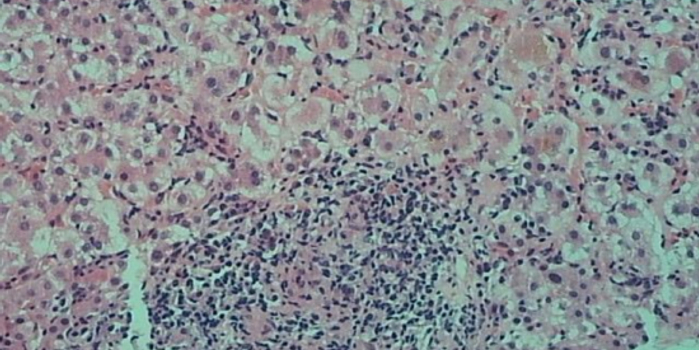

肝穿刺病理图

自身免疫性肝病需要结合患者临床表现、体征、实验室检查(肝功能、免疫球蛋白、自身免疫性抗体等)、肝胆影像学检查和肝脏穿刺病理检查综合判断。尤其对于一些实验室检查不典型的患者,肝穿刺有时成为确诊的重要手段。